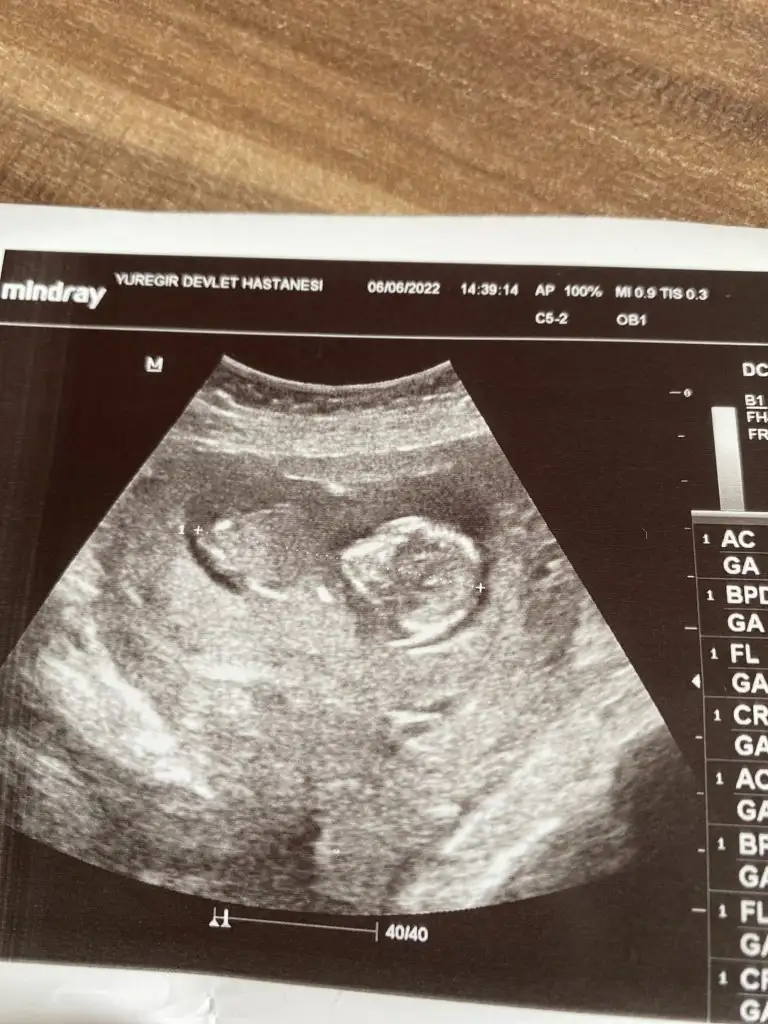

Merhabalar, rica etsem benim yeğenim için de tahminde bulunur musunuzz ☺️ 13+3 karından usg

Eklentiler